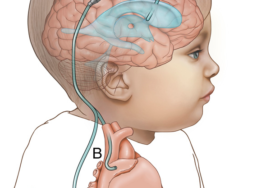

الخوذة ليست شرطًا أساسيًا لكل الحالات. في الزيارة الأولى يتم تقييم درجة التشوه. إذا كان بسيطًا، قد يوصي الطبيب بتغيير وضعيات النوم، وزيادة وقت الاستلقاء على البطن تحت الإشراف، وعلاج أي تيبّس في عضلات الرقبة.

في الحالات المتوسطة إلى الشديدة، قد يُقترح استخدام خوذة طبية مخصصة تساعد على توجيه نمو الجمجمة بشكل متوازن. القرار يعتمد على عمر الطفل ودرجة التشوه.

كيف يتم تشخيص تشوه الرأس؟ وهل يتم قياسه رقميًا؟

يتم التشخيص أولًا بالفحص السريري من خلال النظر واللمس. في بعض المراكز يُستخدم المسح الرقمي ثلاثي الأبعاد لقياس درجة عدم التماثل بدقة وتحويلها إلى أرقام تساعد في متابعة التحسن خلال العلاج.